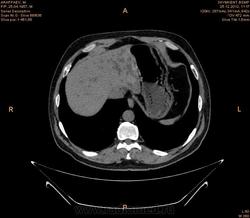

увеличение лимфатических узлов парапанкреатической зоны ,парааортальных ,в области ворот печени,вирсунгов проток расширен,внутри панкреатическую часть холедоха не проследить (возможно на срезах он резко сужен),увеличение головки и крючковидного отростка поджелудочной железы(изоинтенсивна относительно паренхимы поджелудочной железы ),с участками пониженной плотности в структуре ,с отсутствием жировой прослойки с нисходящей горизонтальной частью 12 перстной кишки,высокая вероятность инвазии как забрюшинного жира (переднее параренальное пространство). так и самого органа(рекомендуется контрастное усиление с применением негативного контраста),увеличением размеров левого надпочечника(вероятнее всего метастаз) ,изоинтенсивного исходному органу по плотности с гиподенсивными участками округлой формы в структуре ,участком повышенной плотности,линейной формы по медиальному контуру (вероятнее всего кровоизлияние ),на одном из срезов между увеличенным надпочечником и верхним полюсом правой почки определяется линейная структура изоинтенсивная ткани почки и надпочечника ?(инвазия в периренальное пространство или объемный эффект не скажу точно),гипоинтенсивные относительно печени участки округлой формы с преймущественной локализацией в левой доле (возможно мтс,рекомендуется контрастное усиление ),подковообразная почка ,слева расширенная чашечнолоханочная система ,расширенный верхний сегмент мочеточника (для более подробной информации кт с контрастом -для определения природы обструкции),расширенные внутрипеченочные желчные протоки

Подковообразная почка, с кистами слева, образование надпочечника. К тому же имеет место внутрипеченочная гипертензия. Гепатоспленомегалия. Инфильтрация парапанкреатической клетчатки (не точно). Лимфоузлы в воротах печени (неточно). Холедох я так и не разглядела, если честно.Необходимо дообследование, я думаю. КТ с внутривенным контрастированием хотя бы. Дождемся других мнений....

Спасибо большое.Я начинаюший врач КТ кабинета.Вы мне здорово помогли.Я утром заклюячение отдала не дождавший ваши мнение.Гепатоспленомегалия.Внутипеченочная гипертензия Образование правого надпочечника.Подковобразн.почка гидронефротич.трансформаций левой половины.Образование головки поджелудочн.железы? Рек -но КТ с контрастиров или МРТ исследов.